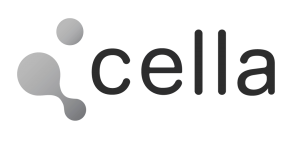

Following multidisciplinary assessment by the Oncology Committee, a right upper pole laparoscopic heminephrectomy was indicated for diagnostic histopathological analysis. Imaging studies were inconclusive and did not allow definitive diagnosis or exclusion of malignancy. Additional imaging performed at the Complejo Hospitalario Universitario de Albacete, including MRI and angio-CT, anticipated significant challenges in vascular localisation and dissection. The renal artery and vein bifurcated within the kidney, beneath the tumour and in close contact with it. Furthermore, the small calibre of these vessels limited precise visualisation of their anatomical course.

Three-dimensional reconstruction enabled precise localisation of the vascular bifurcation, revealing the presence of two arteries and two veins supplying each renal moiety —an anatomically relevant finding that had not been previously identified and was critical for surgical planning.

Detailed 3D anatomical analysis, combined with advanced functionalities such as arterial territory assessment and the ability to work intraoperatively with dual visualisation —3D reconstruction and laparoscopy displayed simultaneously— was a key factor in the success of the procedure.